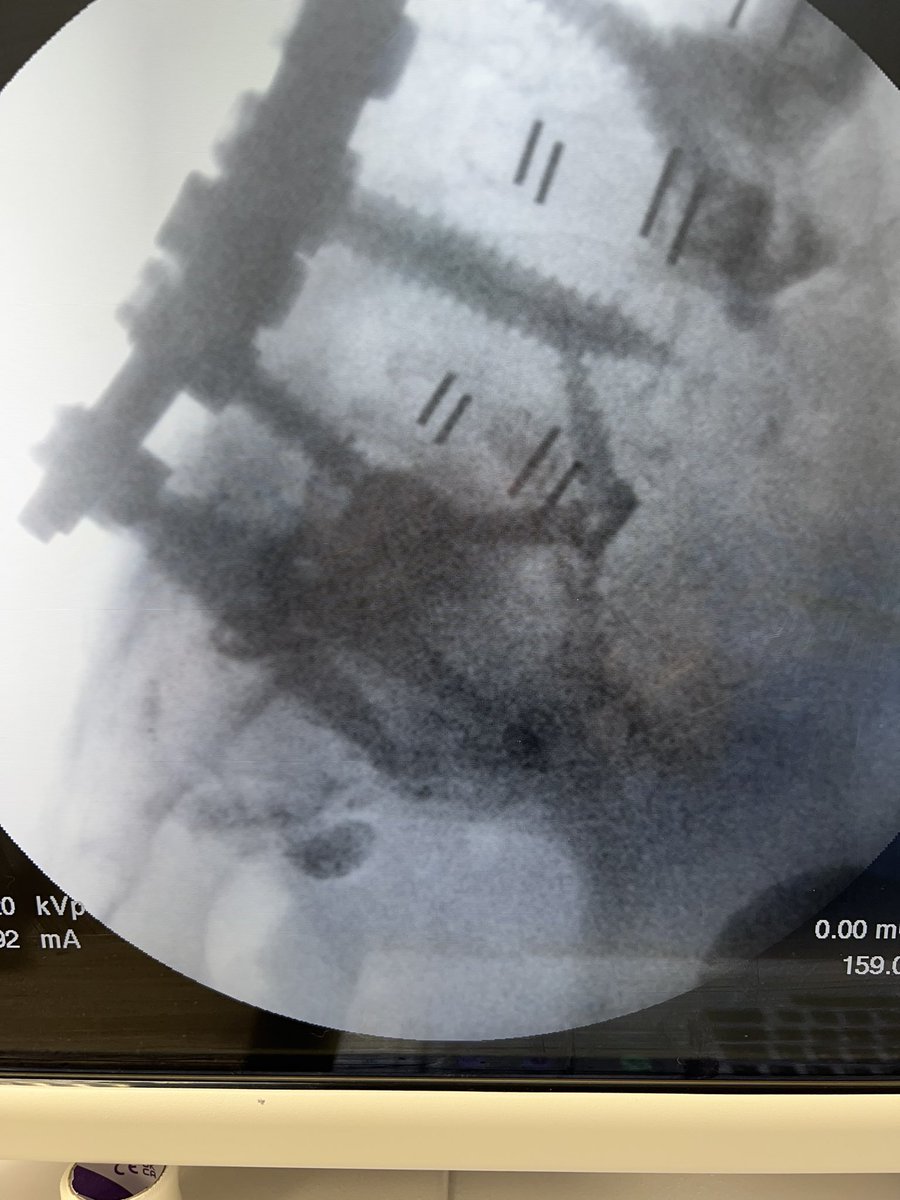

@TheStrykerIVS makes a great product, #SpineJack, that shows up in a lot of cool posts on this and other platforms.

This example was just posted by @neuroradiology - a great example of the genre.